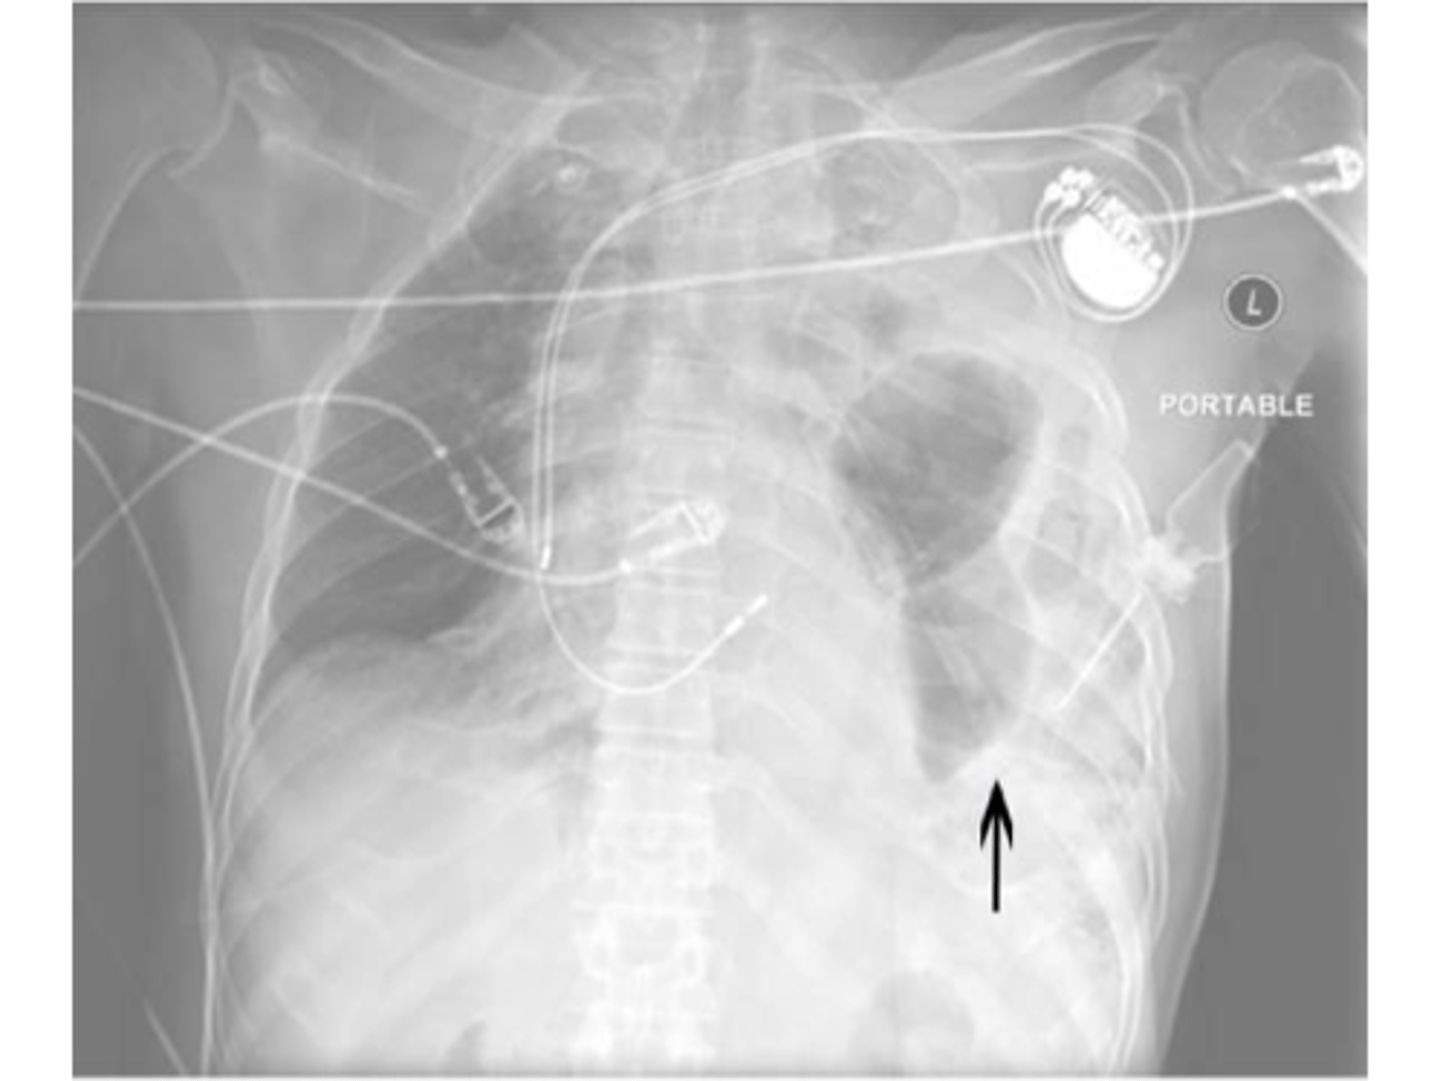

Tension pneumothorax

Hemopnuemothorax

Tension pneumothorax (right)